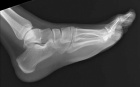

N.H. - 15 year old white male with a slowly growing mass over the plantar aspect of his left foot

Zoom image: Radiological image Radiological image.